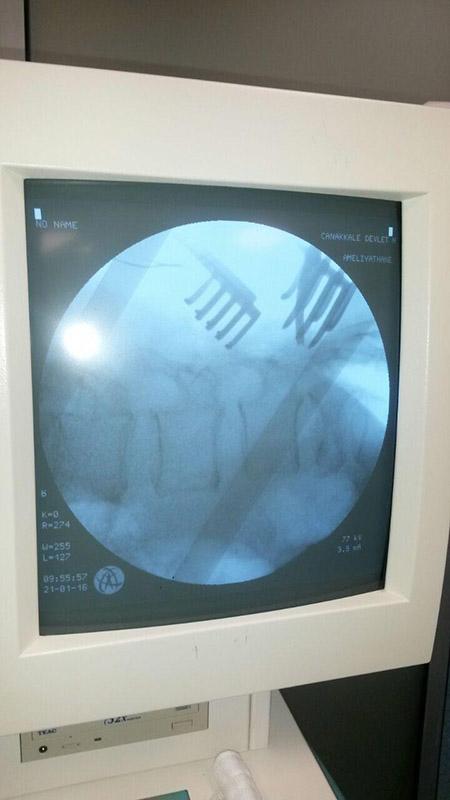

REBORN SPINAL STABILIZATION SYSTEM

Spinal Stabilization System Reborn ® Spinal Fixation System is an implant system used to treat a r...